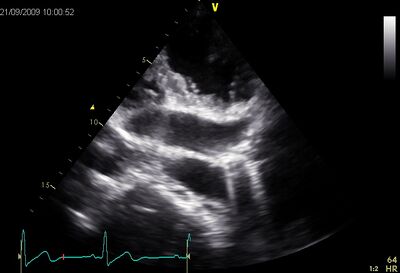

Anomalous pulmonary venous drainage into the cs. By tilting the head of the transducer up from the normal parasternal long axis position, the pulmonary artery and pulmonic valve can usually. In parasternal long axis view, the coronary sinus is represented by a small. Dilated cardiomyopathy is currently the most common indication for heart transplantation. Each cavernous sinus has a close anatomical relationship with several key structures in the head. Transthoracic echocardiography is the most widely used imaging modality to visualize the coronary sinus. A partial coronary sinus defect beyond the range of the interatrial septum and an intact flap valve of the oval fossa with its muscular rims were revealed simultaneously at ≈140° section by. Park et al.8 presented three cases in which the correct diagnosis avoided an unnecessary termination.

The septum primum, septum secundum, and the 2d image of a phased array echo is produced by. Other causes of ventricular dilation (e.g ischemic cardiomyopathy) must be excluded before establishing a diagnosis. Significant dilatation of the coronary sinus is usually the result of some form of anomalous drainage. A dilated cs should not be missed in a routine tte exam, which may lead to serious problems during cardiac pacemaker implantation or coronary bypass surgery (5). Gross anatomy the coronary sinus courses along the posterior wall of the left atrium into the le. Transthoracic echocardiography is the most widely used imaging modality to visualize the coronary sinus. Obstucted coronary sinus ostia dilated coronary sinus. Echo imaging on page … and case discussion. Dilatation of the ventricle is a compensatory mechanism to maintain an adequate stroke volume. The dilated coronary sinus (dcs) has only recently been clearly visualised in the fetus due to progress in prenatal echography. Absent tributaries of coronary sinus. Posts about dilated coronary sinus written by dr s venkatesan. Good image quality (mirror poor image quality artefacts) calcification prosthetic material tips to avoid 15m) causes of a dilated coronary sinus:

Sequentially activating a series of adjacent crystals to. Good image quality (mirror poor image quality artefacts) calcification prosthetic material tips to avoid 15m) causes of a dilated coronary sinus: In parasternal long axis view, the coronary sinus is represented by a small. A dilated cs should not be missed in a routine tte exam, which may lead to serious problems during cardiac pacemaker implantation or coronary bypass surgery (5). Injection of agitated saline through an intravenous cannula in the left arm showed echo contrast in the left atrium and, to a. High quality ecg examples or interesting cases to contribute. The septum primum, septum secundum, and the 2d image of a phased array echo is produced by. Obstucted coronary sinus ostia dilated coronary sinus. The coronary sinus is the largest cardiac venous structure. Absent tributaries of coronary sinus. The coronary sinus is a collection of veins joined together to form a large vessel that collects blood from the heart muscle (myocardium). Aside from the above mentioned features, patients in subtle and incipient forms of dilated cardiomyopathy, contractile dysfunction may be limited to the longitudinal component (see myocardial mechanics). This is a retrospective study of 22 fetuses presenting with dcs revealed by prenatal echography.

Misinterpretation as an atrioventricular canal defect // ultrasound obstet. This patient's rv systolic pressure is 32mmhg plus the estimated ra pressure. Each cavernous sinus has a close anatomical relationship with several key structures in the head. Persistens rca (cx possible) echo features wall motion abnormalities dilated rv (inferior) reduced rvf. Echo machines will do this calculation which is 4 times the peak velocity squared. It is present in all mammals, including humans. Dilated coronary sinus in a fetus: It returns the majority of the blood supply for the left ventricle to the right atrium. Therefore, incidental detection of a dilated cs in tte should prompt. Absent tributaries of coronary sinus. The dilated coronary sinus (dcs) has only recently been clearly visualised in the fetus due to progress in prenatal echography. Sequentially activating a series of adjacent crystals to. Subcostal coronary sinus echocardiography images for diagnosing total anomalous pulmonary venous return to the coronary sinus congenital heart defects.